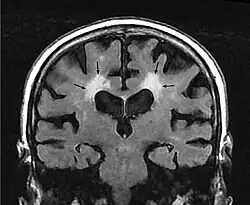

En la Tomografía Computarizada, la leucoaraiosis se observa como regiones con menor densidad, más oscuras que las circundantes, es decir áreas hipodensas, en Imagen por Resonancia Magnética se define como lesiones con mayor intensidad de señal es decir áreas hiperintensas, por presentar un aspecto más brillante que las zonas aledañas. Estas imágenes pueden verse en las regiones próximas a los ventrículos cerebrales, corona radiata y centro semioval.[9] Se han utilizado escalas cualitativas como la de Fazekas para determinar el grado de las lesiones:

- Grado 0 corresponde a ausencia de lesión.

- Grado 1 lesiones focales.

- Grado 2 lesiones confluentes iniciales.

- Grado 3 cuando las lesiones difusas son muy extensas y comprenden regiones cerebrales completas.